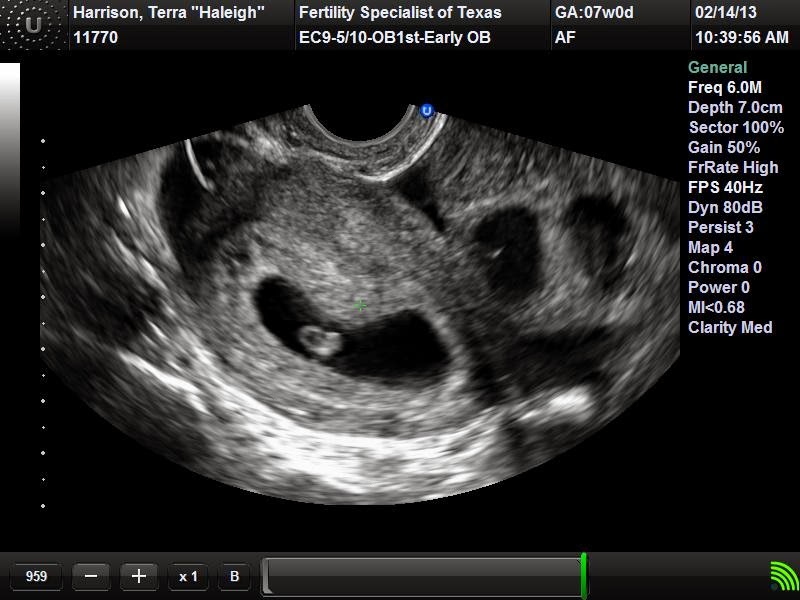

- 2/14/13: Heart Beat

- We got to hear the baby’s heartbeat for the first time today!